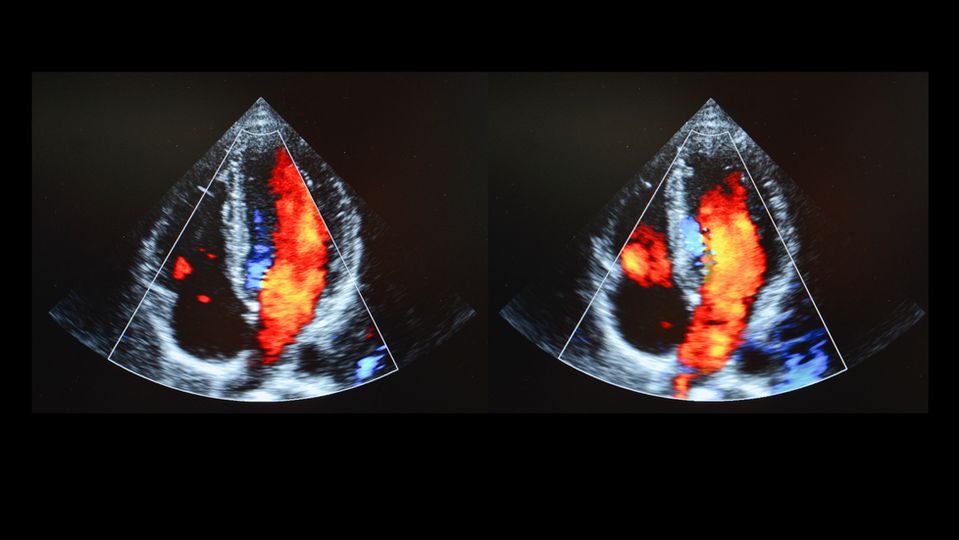

Imaging with ultrasound is done with a trained Diagnostic Medical Sonographer who will use gel and a transducer to image soft tissue, and vascular blood flow, and monitor fetal development in pregnancy or OB.

There are preps for abdominal, pelvic, cardiac, and OB imaging to help our skilled ultrasound technologist visualize specific body parts. OB and pelvic examinations require a full bladder for imaging. Abdominal scans are usually scheduled in the mornings so you can come fasting. Cardiac ultrasounds require no caffeine or stimulants. See our full prep instructions below.